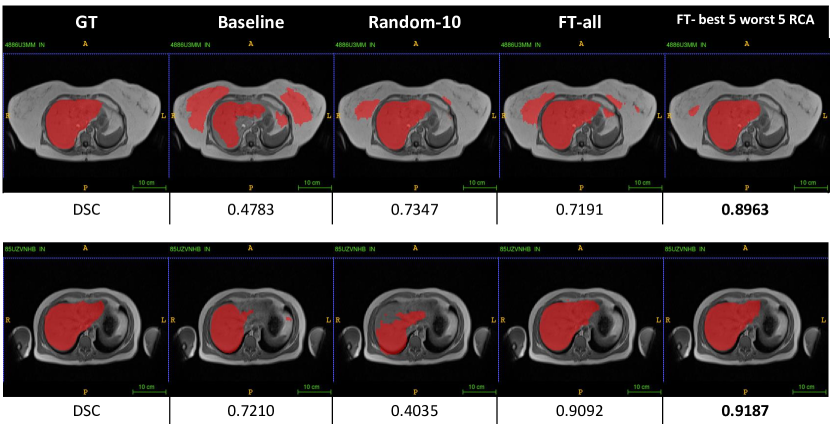

3.4 Fine-tuning in Right Kidney Segmentation

From the three different strategies of DARCA in liver segmentation, we can see that fine-tuning with DARCA gives better results, less time-consuming (compared to training from scratch), and no iterative scheme needed. Also, from the results in liver segmentation (Table 2), combination of best-5 and worst-5 subjects always gives better or similar results than using all of the subjects from domain T, in all strategies. To validate these results, we also explore DARCA-FT in a different task: right kidney segmentation.

Similarly, the best results of right kidney segmentation with fine-tuning are achieved when we combine best-5 and worst-5 subject selection (see Table 4). The result (DSC: 0.716 with RCA selection) is better than when fine-tuning with all of the subjects from T (DSC: 0.658), and similar to when we train from scratch using all target subjects. This means we could cut the processing and annotation time. Figure 5 depicts some examples on how DARCA-FT with combination of best-5 and worst-5 subject selection improves the baseline and gives the best segmentation accuracies.

In this scheme, DARCA shows its potential to leverage the highest and lowest confident subjects, to be incorporated in the domain adaptation process. We demonstrated that DARCA with few labeled data can perform similarly and/or better to full-size labeled target data. In the examples of Figure 4 and Figure 5, DARCA with best-5 and worst-5 subjects show consistent results across different tasks (liver and kidney segmentation).